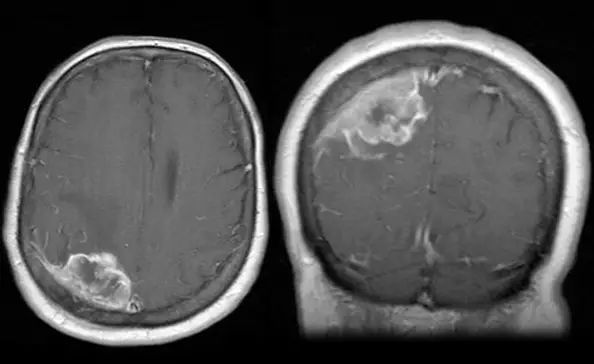

对于表现为脑膜瘤症状的患者,头部CT扫描经常作为较初的影像学检查,但头颅MRI平扫或增强扫描对诊断很有必要。在许多情况下,脑膜瘤的放射学检查结果足以确诊。一例表现为新发癫痫但没有其他症状的55岁女性患者进行了头部CT平扫(左)。影响学检查显示右顶叶轻微水肿,提示潜在病变。MRI轴位T1加权像(右)提示病灶均匀强化,病变位于硬脑膜,表现为经典的脑膜瘤征象。